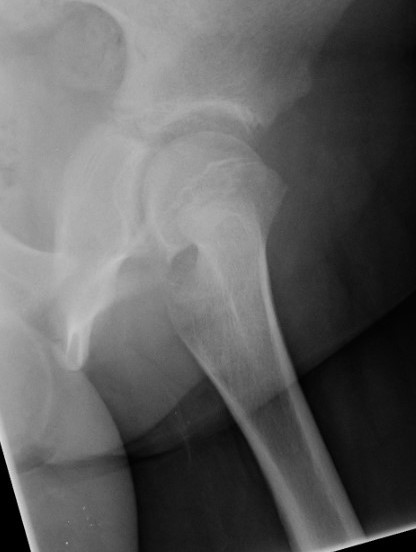

AP Xray

Widened eipiphysis

Klein's Line

- line along superior neck should transect part of epiphysis

Mild slip with failure of Klein's line to transect epiphysis

Lateral xray

Mild and moderate SCFE on left hips